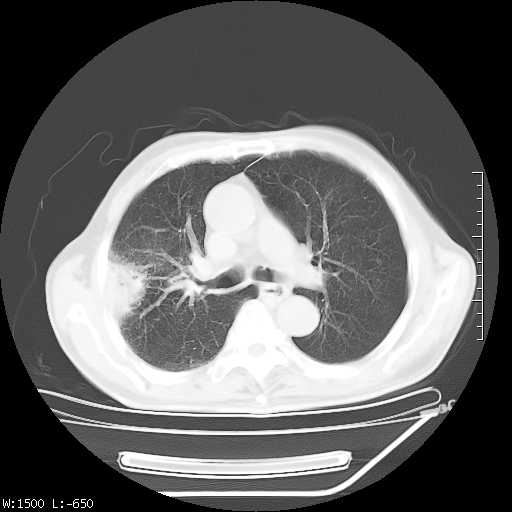

标题: CT23994:男、72、咳嗽、气短两月余,近来消瘦。 [打印本页]

标题: CT23994:男、72、咳嗽、气短两月余,近来消瘦。

右上肺实变,与胸膜关系密切,右肺容积缩小,隆突下淋巴结增大,考虑1 肺结核 2 肺癌

右上肺大片状密度增高影,与胸膜关系密切,内见低密度透亮影,胸膜下可见三角形不张影,左下肺沿支气管走形结节影,纵膈内淋巴结显示。考虑结核并疤痕性不张可能性大,建议穿刺活检,排除肺泡癌。